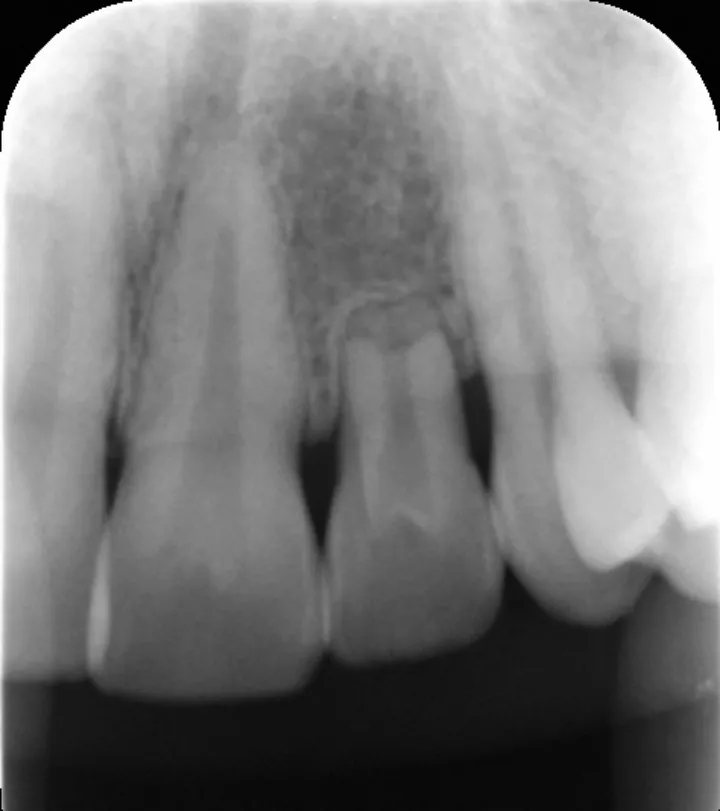

图 21 :术前临床检查。

图 22 :术前 X 线检查。

图 26 :术后 X 线检查。